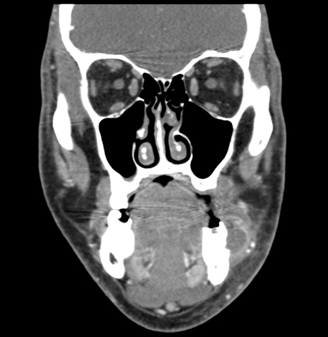

The results of contrast-enhanced maxillofacial computed tomography (CT) scans revealed an odontogenic facial soft-tissue abscess (Figures 1-3). There were partially missing first and second left mandibular molars with an adjacent rim-enhancing perimaxillary hypodensity consistent with a periapical abscess. Regional cellulitis and lymphadenopathy were present.

Figure 2. Coronal contrast-enhanced CT showing the same fluid collection as it relates to an area of fractured teeth.